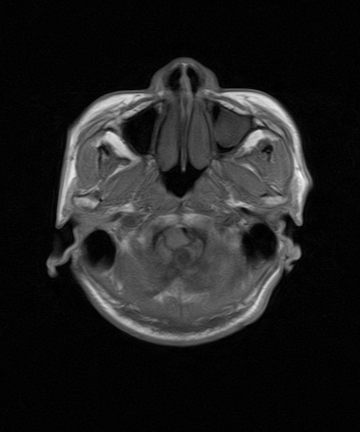

考虑第四脑室室管膜瘤并梗阻性脑积水;部分性空蝶鞍;左侧上颌窦粘膜下囊肿。

加左上颌窦囊肿

2、左侧上颌窦及蝶窦囊肿。